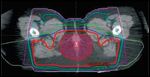

Axial image from conventional 3-dimensional radiation planning for a patient with a T2N2M0 (IIIB) squamous cell carcinoma of the anal canal.FIGURE 3

Axial image from intensity-modulated radiation therapy planning for the same patient.FIGURE 4

RTOG 05-29 is a prospective phase II efficacy trial utilizing IMRT in the treatment of anal canal cancer.[39] All patients received concurrent 5FU and MMC. In this study, IMRT was delivered by “dose painting,” in which different target volumes are treated concurrently but different-sized radiation fractions are used for different target structures, which is achievable with IMRT. The doses prescribed to elective nodal areas depended on the stage of disease, and the total dose to gross disease ranged from 50.4 to 54 Gy. As an example, the patient depicted in Figures 2-9 with T2N2M0 disease might have received 1.5 Gy/day (to a total of 45 Gy) to the uninvolved (elective) inguinal and upper pelvic regions, 1.68 Gy/day (to a total of 50.4 Gy) to an involved right pelvic lymph node (which measured ≤ 3 cm), and 1.8 Gy/day (to a total of 54 Gy) to the gross anal canal tumor.